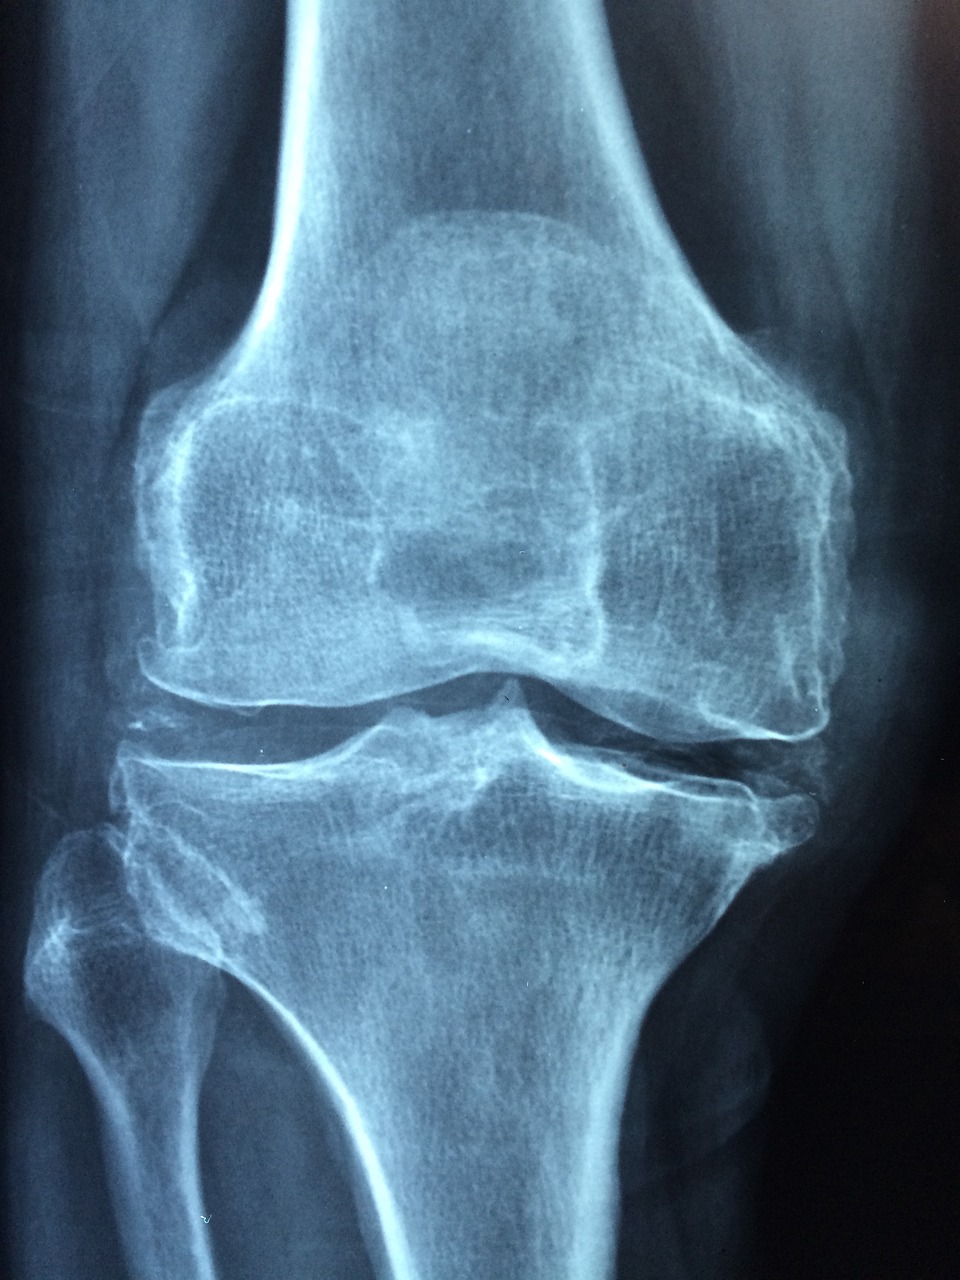

골다공증의 핵심은 뼈가 약해지고 연약해지는 뼈 질환입니다. 그리스어에서 유래한 이 단어 자체가 '다공성 뼈'로 번역돼 이 질환의 주요 특징인 골밀도 감소를 적절하게 표현하고 있습니다. 건강한 상태의 뼈는 치밀하고 튼튼하지만 골다공증은 뼈를 약하게 만들어 사소한 낙상이나 일상생활에서도 골절에 취약합니다.

뼈는 밀도가 떨어지면 다공성이 되고 부서지기 쉬워지며, 마치 현미경으로 관찰하면 벌집 같은 구조를 닮게 됩니다. 이렇게 다공성이 증가하면 뼈의 구조적 무결성이 손상되고, 특히 엉덩이, 척추, 손목에 골절이 발생하기 쉽습니다. 흔히 골다공증은 골절이 발생할 때까지 눈에 띄는 증상 없이 진행되기 때문에 소리 없는 질병이라고 불립니다. 시기 적절한 치료를 위해서는 초기 증상과 위험 요소를 파악하는 것이 중요합니다.

폐경 후 여성과 위험인자가 있는 개인에게 특히 중요한 골밀도 검사는 X선을 이용하여 골밀도를 측정합니다. 조기 발견을 통해 적시에 개입하고 예방 조치를 취할 수 있습니다.